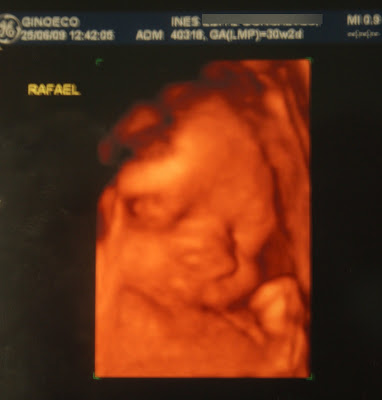

O Rafael:Os braços, as pernas e o corpo todo do bebê continuam sendo recheados de tecido adiposo -- e finalmente os membros são proporcionais em relação ao tamanho da cabeça. Ele pesa cerca de 1,5 quilo e já se parece mais com um recém-nascido. O comprimento total é de 41 centímetros.

Mais uma boa semana, ainda mais depois de 5º feira ter visto o meu bebbecas e saber q está tudo bem, que ele está a crescer bem e que corre tudo dentro da normalidade!

Sobre a posição do Rafael... como sabem ele mudou de posição de 6ª feira da semana passada para 5ª, mas sinceramente eu não noto (nem notei) mudanças nos movimentos dele, nem onde sinto os soluços, continuo a senti-los da mesma forma e nos mesmo sitio o q já antes me fazia crer q ele já estaria de cabeça para baixo... estranho!